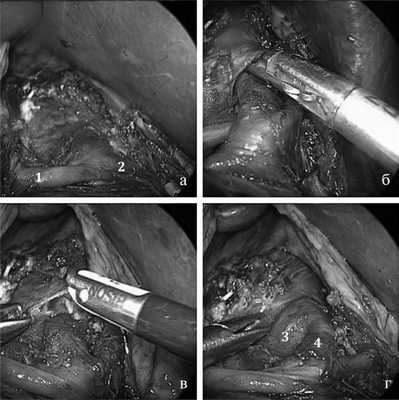

После создания карбоксиперитонеума 12 мм рт.ст. осуществляли доступ к чревному стволу и его ветвям через печеночно-желудочную связку. Операция заключалась в полном освобождении ЧС, а также его ветвей от сдавления путем рассечения, а иногда путем иссечения сдавливающих его тканей: срединной дугообразной связки диафрагмы, внутренних ее ножек и нейрофиброзной ткани чревного сплетения (рис. 4).

Рис. 4. Эндофотография основных этапов лапароскопической декомпрессии чревного ствола. а — вид после мобилизации общей печеночной артерии (1) и левой желудочной артерии (2); б — мобилизация срединной дугообразной связки; в — рассечение срединной дугообразной связки; г — вид после декомпрессии чревного ствола: аорта (3), чревный ствол (4).

По данным интраоперационной ревизии было установлено, что срединная дугообразная связка диафрагмы в сочетании с нейрофиброзной тканью чревного сплетения являлась основной причиной компрессионного стеноза ЧС во всех наблюдениях.